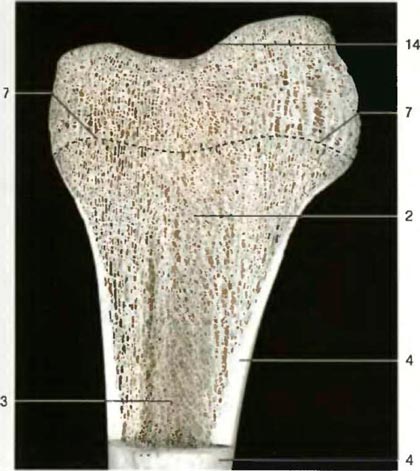

| Венечный разрез через проксимальный эпифиз большеберцовой кости взрослого человека. Видна зона уплотнения кости на месте бывшей эпифизарной пластинки (пунктирная линия) |

| Кости скелета состоят из двух различных частей: губчатого и компактного вещества. Перекладины губчатого вещества хороню приспособлены к механическим воздействиям, показанным векторными структурами. Пространство между перекладинами заполнено костным мозгом, зоной кроветворения. На компьютерной и магнитно-резонансной томограммах изображения костей, мышц и мягких тканей различны. Изображение при компьютерной томографии аналогично рентгеновскому, поэтому зоны максимального накопления, например кости, белого цвета, а зоны минимального накопления, например жировая ткань, - черного цвета. По контрасту интенсивность сигнала при магнитно-резонансной томографии, получаемая при помощи магнитного воздействия, а не рентгеновских лучей, очень сильно отличается, и плотные участки костей выглядят черными, а мягкие ткани, такие как костный мозги жировая ткань, - белыми (для сравнения смотрите рисунки). Надкостница имеет сильно развитую сеть нервных волокон и является структурой, необходимой для питания костей, их кровоснабжения, роста и репарации. | |||